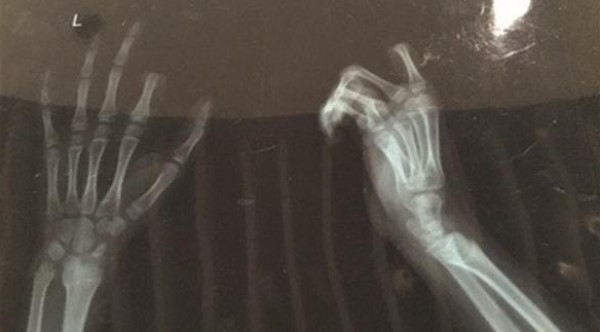

وأصيبت العائلة بالصدمة جراء هذا التصرّف غير المتوقع، قبل أن يتم نقل الفتى – مع إصبعه المبتور - إلى المستشفى حيث أجرى الأطباء عملية جراحية استغرقت 3 ساعات.

وعلى الرغم من قيام الأطباء بإعادة تركيب الإصبع المبتور، فإن الجرّاح المسؤول أكد أن نتيجة العملية لن تُعرف قبل أسبوع على الأقل.